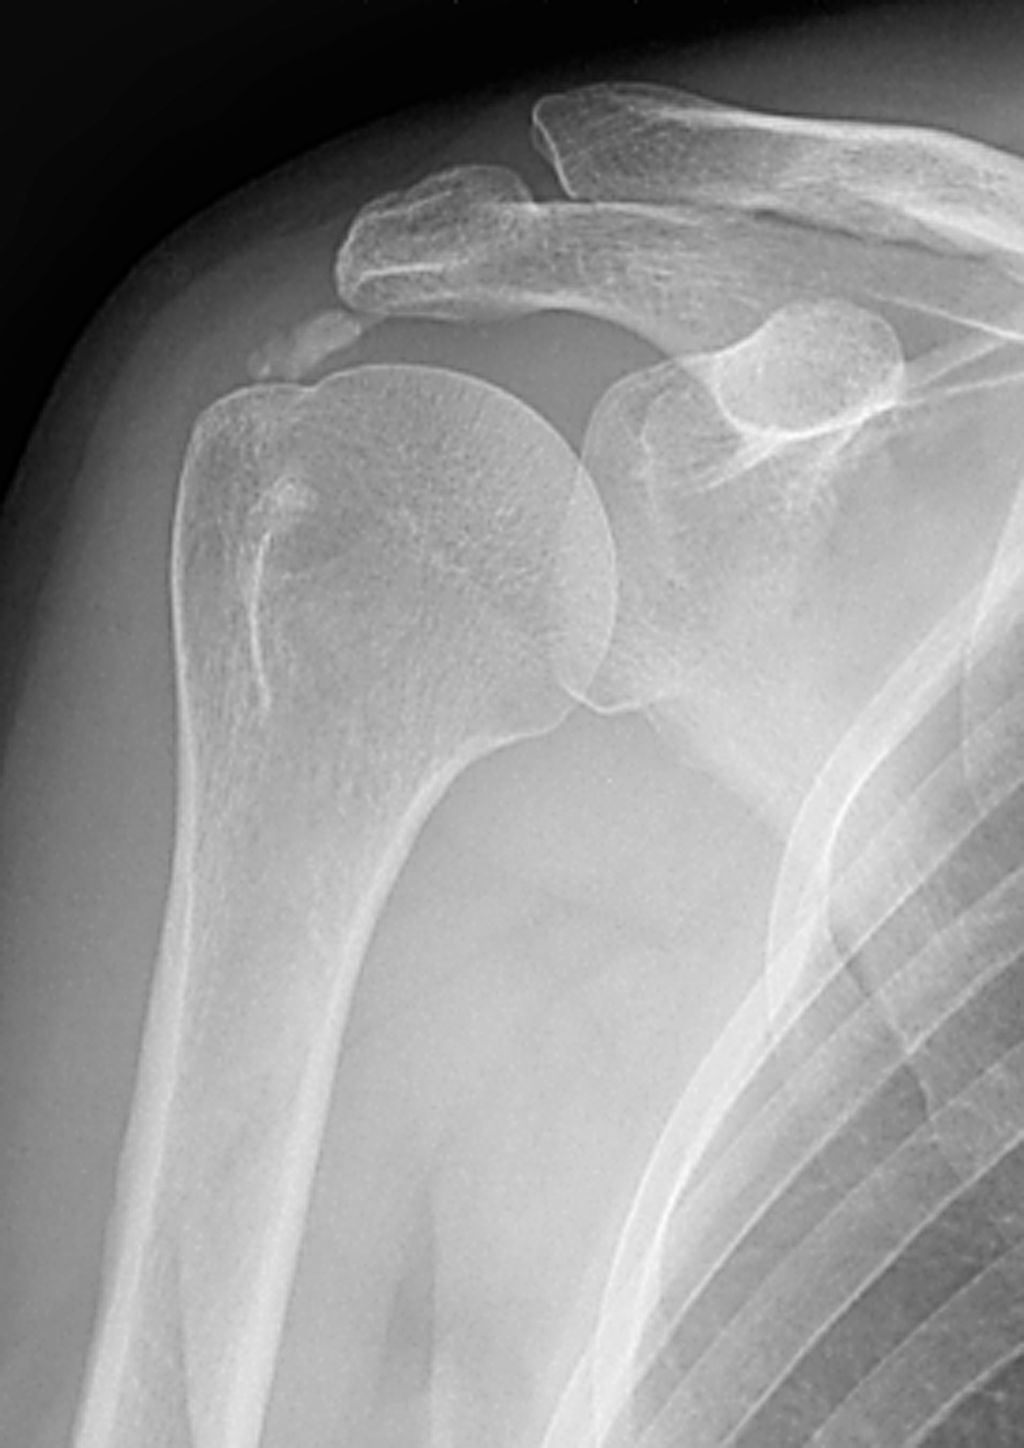

Tendinitis calcificante

Depósitos amorfos de hidroxiapatita en tendones, más frecuente en el manguito rotador (supraespinoso), pero también en cadera, codo y rodilla. Puede ser asintomática o causar dolor agudo durante la fase de reabsorción. Resolución espontánea en muchos casos.

Calcinosis tumoral

Grandes masas globulares periarticulares, densamente calcificadas, típicamente en caderas, hombros, codos y rodillas. Puede ser primaria (familiar) o secundaria a insuficiencia renal. No es neoplásica, a pesar de su nombre. Las masas pueden ser asintomáticas o causar compresión local.